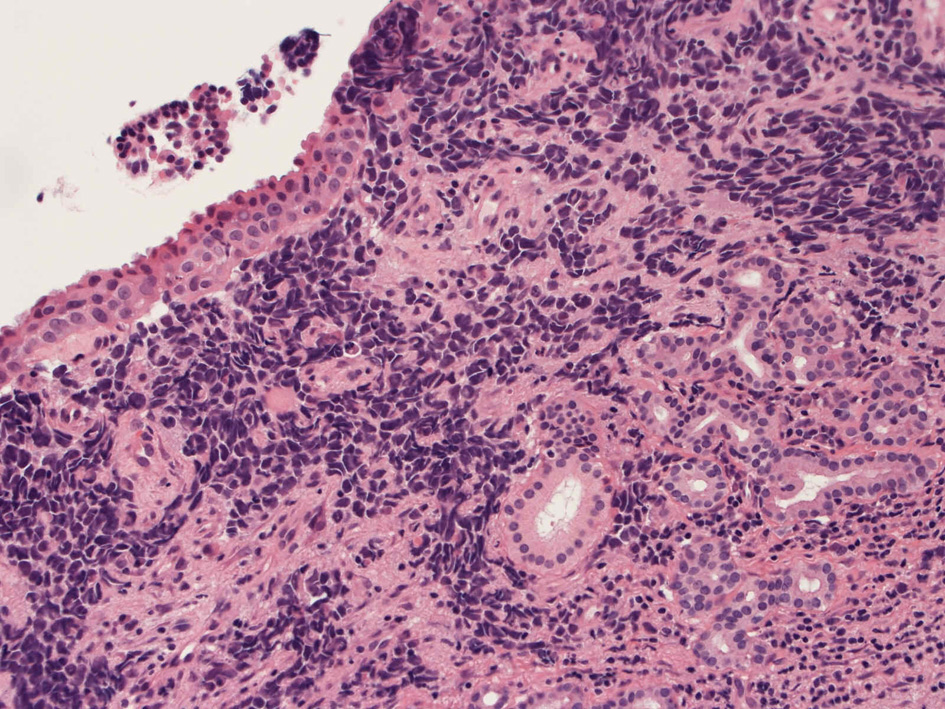

40歳女性 鼻粘膜腫瘤

右頸部のしこりを自覚。近医MRIで頸部多発リンパ節腫大あり当院を紹介される。右顎下, 右鎖骨上窩にも多数のリンパ節を触れる。穿刺細胞診ではcarcinoma疑い。右鼻腔, 上顎洞にも腫瘤が認められリンパ節腫大との関係を調べるために鼻腔腫瘤の生検が行われる。

病理組織所見

HE01.jpg